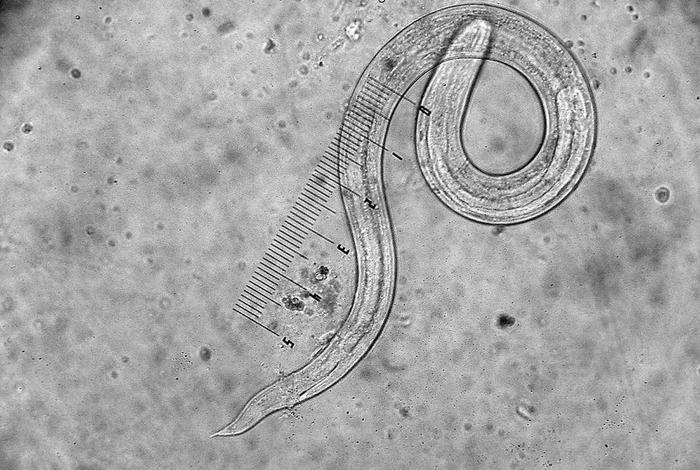

线形动物是一类特殊的生物群体,其中许多种类以寄生生活为生存方式。这些微小的生物拥有独特的生理结构和特点,使其在寄生环境中得以生存并繁衍。今天,我们将深入探讨这些寄生生活的线形动物以及它们适应寄生生活的结构特点。

线形动物作为寄生生物,其消化系统为适应寄生环境而发展出独特的特点。它们的消化系统相对简单,但足以满足寄生生活的需求。这些动物的口部通常具有尖锐的牙齿或刺,用于附着在宿主身上并吸取营养。它们的肠道非常短,吸收能力强,能够迅速摄取宿主体内的营养物质。这种高效的消化系统使得线形动物能够在寄生环境中快速获取所需营养,适应不同的生存环境。

线形动物通过其特殊的表皮细胞吸收宿主环境中的养分。它们的表皮细胞具备高效的渗透作用,能够吸收宿主体内的水分、矿物质和营养物质。这种吸收方式使得线形动物能够在寄生环境中迅速获取所需物质,维持生命活动。

虽然线形动物体型微小,但它们具备灵活的运动能力。这些生物可以通过身体的弯曲和扭动,在宿主体内迅速移动,寻找更适宜的生活环境。这种运动能力使得它们能够在寄生环境中更好地适应和生存。

寄生生活的线形动物通常具有强大的生殖能力。它们可以在短时间内快速繁殖,提高种群数量。这种强大的生殖能力使得它们在寄生环境中更容易存活并繁衍后代。

为了成功寄生在宿主身上,线形动物发展出抵抗宿主免疫系统的机制。它们可以通过分泌特殊物质来抑制宿主的免疫反应,避免被宿主免疫系统攻击。它们的身体结构也能有效抵抗宿主体内的消化酶,保护自身不受伤害。

寄生生活的线形动物具备独特的结构特点和适应性,使它们在寄生环境中得以生存并繁衍。从消化系统结构、吸收系统、运动能力、生殖能力以及抵抗宿主免疫系统的机制等方面,我们可以看到线形动物如何适应寄生生活。这些微小的生物展现出的生命力和适应能力令人惊叹。通过深入了解这些生物的特点和适应性,我们可以更好地了解生命的多样性和复杂性。